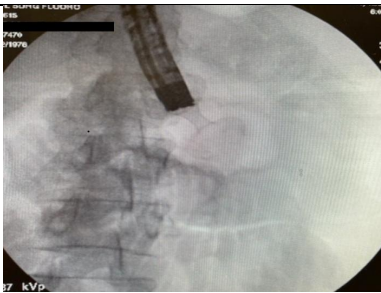

The procedure involved passing a guide wire beyond the obstruction using a gastroscope using contrast dye under fluoroscopy. Then the 8.5 Fr nasobiliary cannula (Boston Scientific, Marlborough, MA) was passed over the guide wire beyond the luminal obstruction and to achieve that a balloon extraction catheter (Boston Scientific, Marlborough, MA), was used since the length of the cannula was not adequate (Figure 3). Then using a linear array echoendoscope (Olympus, Center Valley, PA) from the stomach a suitable jejunal segment beyond the obstruction was selected by passing the diluted contrast agent through the cannula. Using both the images from the echoendoscope and fluoroscope 20 mm x 10 mm lumen apposing metal stent (LAMS) Axios (Boston Scientific, Marlborough, MA) was successfully deployed (Figures 4, 5, and 6).

Figure 3. Nasobiliary catheter in jejunum